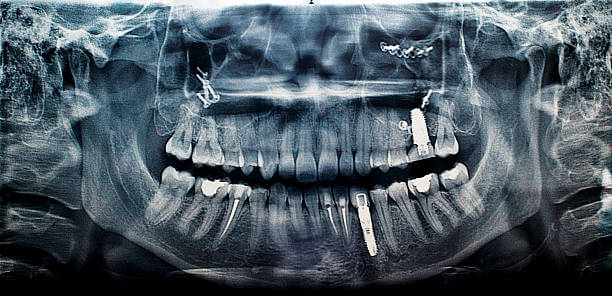

- 엑스레이 촬영 → 잇몸뼈 흡수 여부 확인

- 임플란트 주위 잇몸 검사 → 출혈, 붓기, 주머니 깊이 확인

- 교합 검사 → 물리는 힘이 과도하지 않은지 점검

- 보철물 점검 → 나사 풀림, 균열 여부 확인